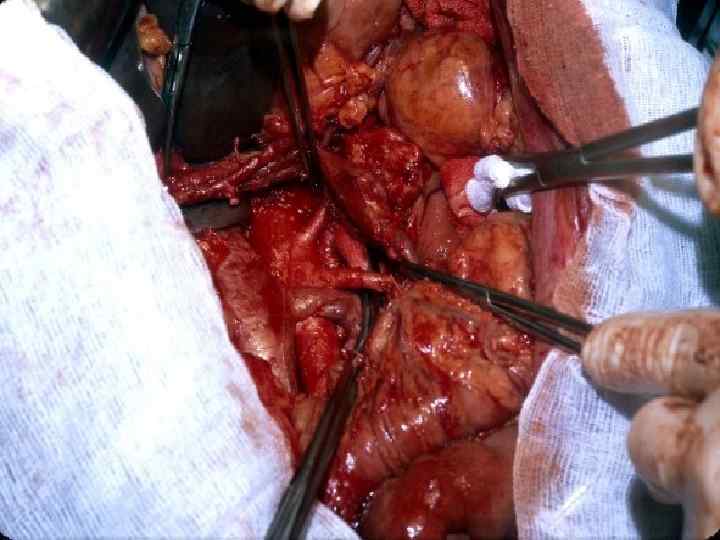

Этапы стандартной ГПДР • • • 1. Мобилизация 12 -перстной кишки 2. Выделение трубчатых структур гепато-дуоденальной связки 3. Выделение верхней брыжеечной вены 4. Мобилизация и отсечение дистальной части холедоха 5. Мобилизация и пересечение начальной части тощей кишки 6. Пересечение гепатикохоледоха после мобилизации желчного пузыря • 7. Пересечение поджелудочной железы по перешейку • 8. Пересечение связок крючковидного отростка, удаление комплекса • 9. Реконструктивный этап

Резекция чревного ствола и общей печёночной артерии при выполнении ДСРПЖ Вид резекции Циркулярная резекция чревного ствола Всего Число больных с пластикой 4 без пластики 11 15